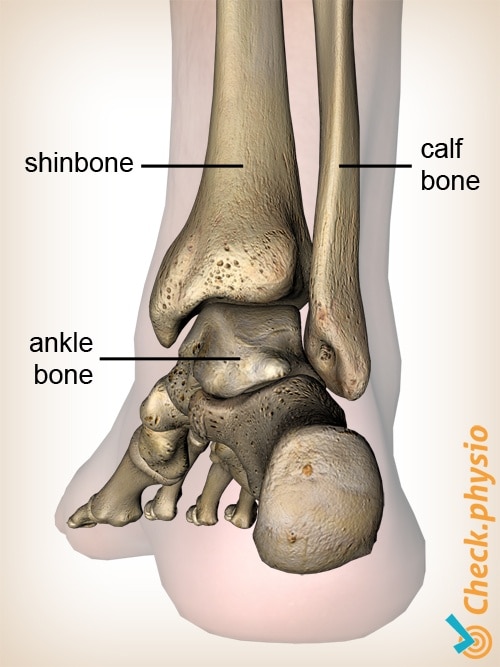

Анатомия фибулы: Подробные фотографии и схемы